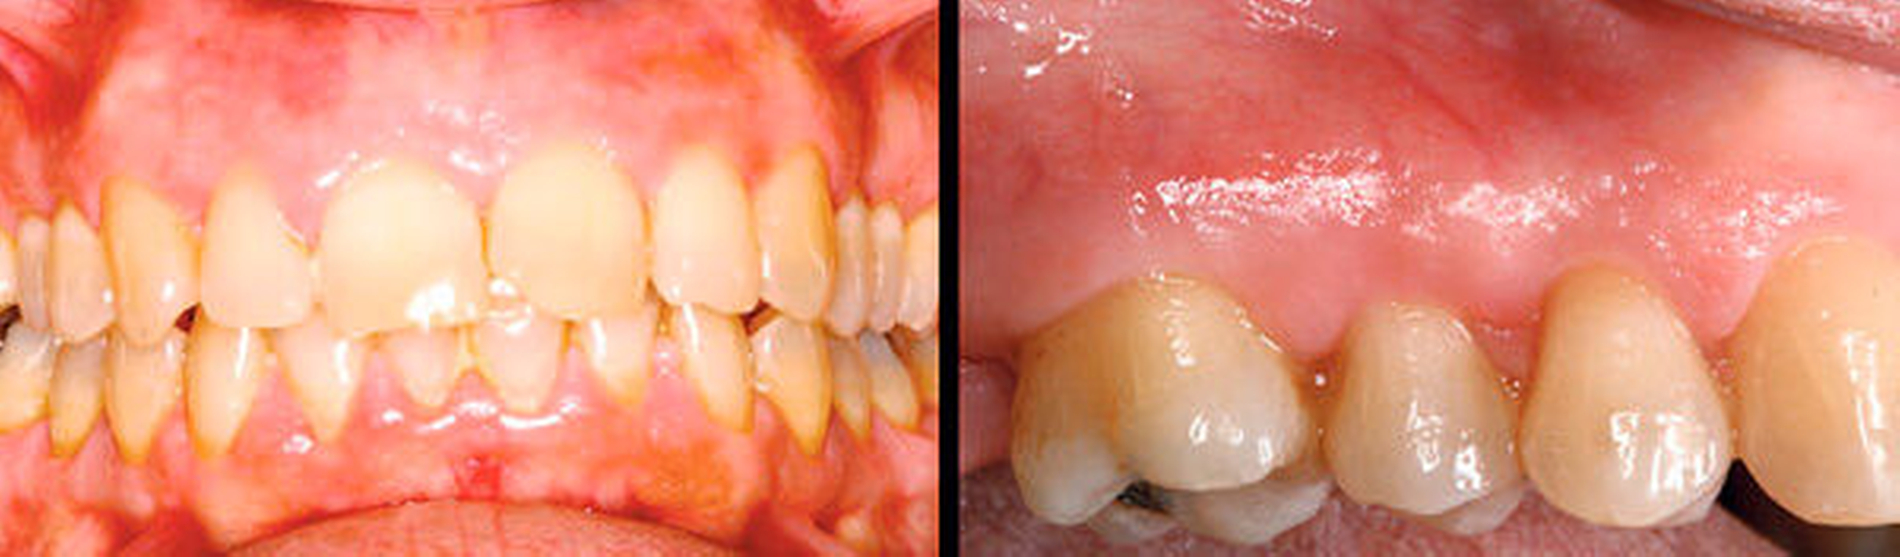

Parodontitis ist eine chronische, multifaktorielle Entzündungskrankheit, assoziiert mit einem dysbiotischen Plaque-Biofilm und gekennzeichnet durch die fortschreitende Zerstörung des Zahnhalteapparats. Die Parodontitis ist durch eine Entzündung charakterisiert, die zum Verlust parodontalen Attachments führt. Während die Bildung des bakteriellen Biofilms die Zahnfleischentzündung auslöst, ist die Erkrankung Parodontitis durch drei Faktoren gekennzeichnet:

- den Verlust des Zahnhalteapparats, erkennbar durch klinischen Attachmentverlust (clinical attachment loss – CAL) und röntgenologisch sichtbaren Knochenabbau,

- das Vorhandensein parodontaler Taschen,

- gingivale Blutung.

Schwere der Erkrankung

Der Grad der bei der Diagnose vorliegenden parodontalen Destruktion beschreibt die Schwere der Erkrankung, die sich nach der Größe des Attachmentverlusts oder des parodontalen Knochenabbaus bemisst. Der Schweregrad muss den Zahnverlust einbeziehen, der auf die Parodontitis zurückzuführen ist. Eine weitere Dimension der Schwere der Erkrankung ist die Komplexität der Behandlung. Faktoren wie zum Beispiel Sondierungstiefen, Art des Knochenabbaus (vertikal und/oder horizontal), Furkations-beteiligung, Zahnlockerung, Anzahl fehlender Zähne, Bisskollaps und erhöhte Komplexität der Behandlung müssen in die diagnostische Klassifizierung einbezogen werden. Ebenso sollte das Ausmaß der Erkrankung – definiert durch die Anzahl und Verteilung der Zähne mit erkennbarem parodontalen Abbau – in die Klassifizierung eingearbeitet werden.